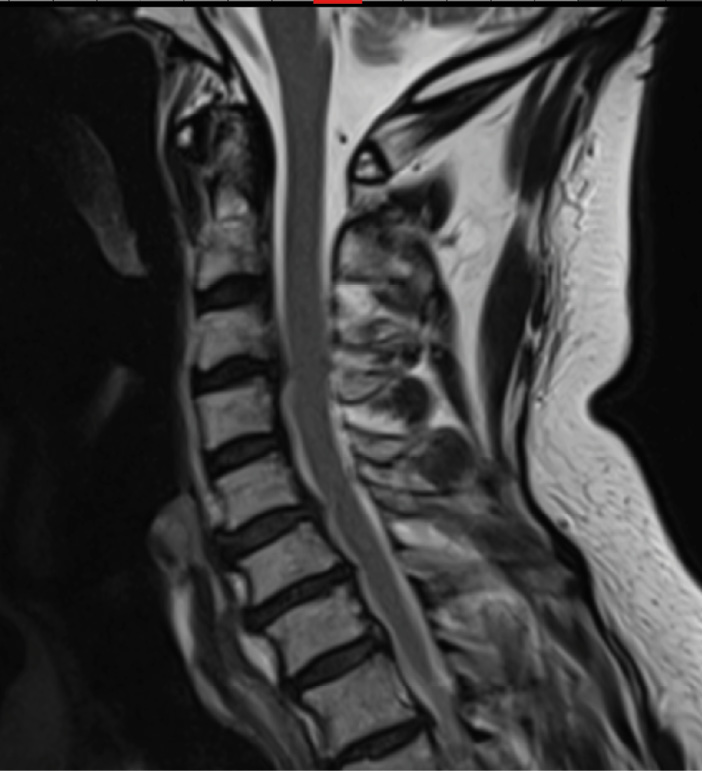

Pre-op MRI demonstrates partial disc height collapse and foraminal stenosis at C5-6 and C6-7.